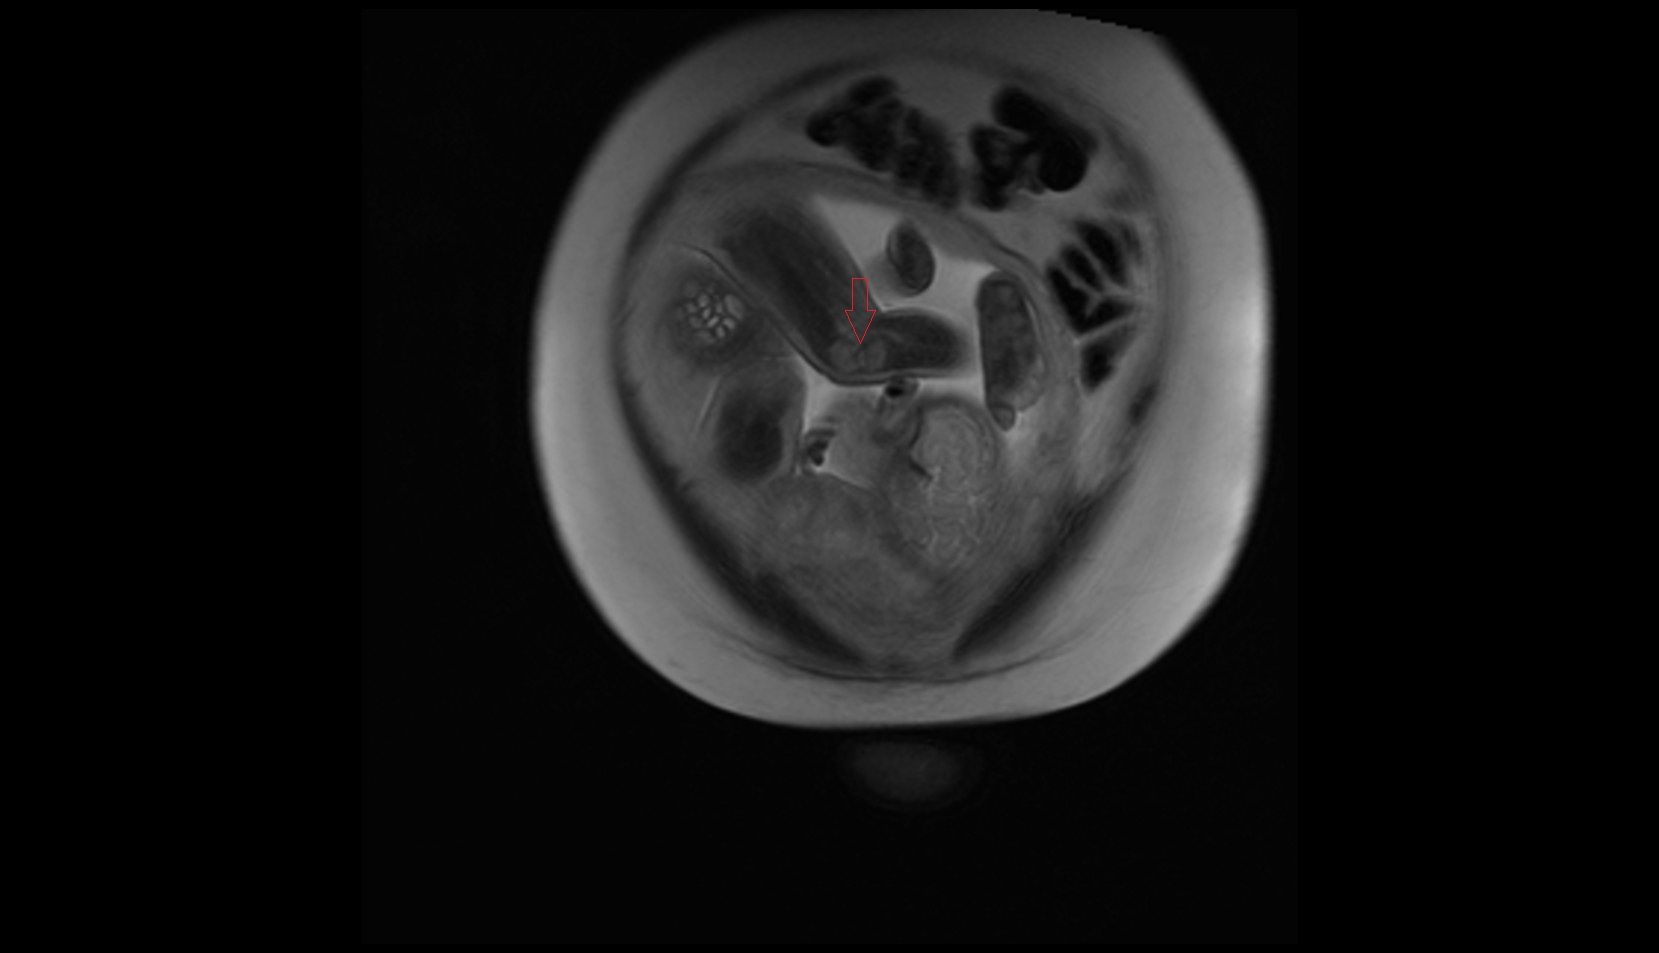

- Placenta

- Uterus (pregnancy)

- Amniotic fluid

- Umbilical cord

- Fetal brain

- Fetal caudate nucleus

- Fetal thalamus

- Fetal pons

- Fetal cerebellum

- Fetal Heart